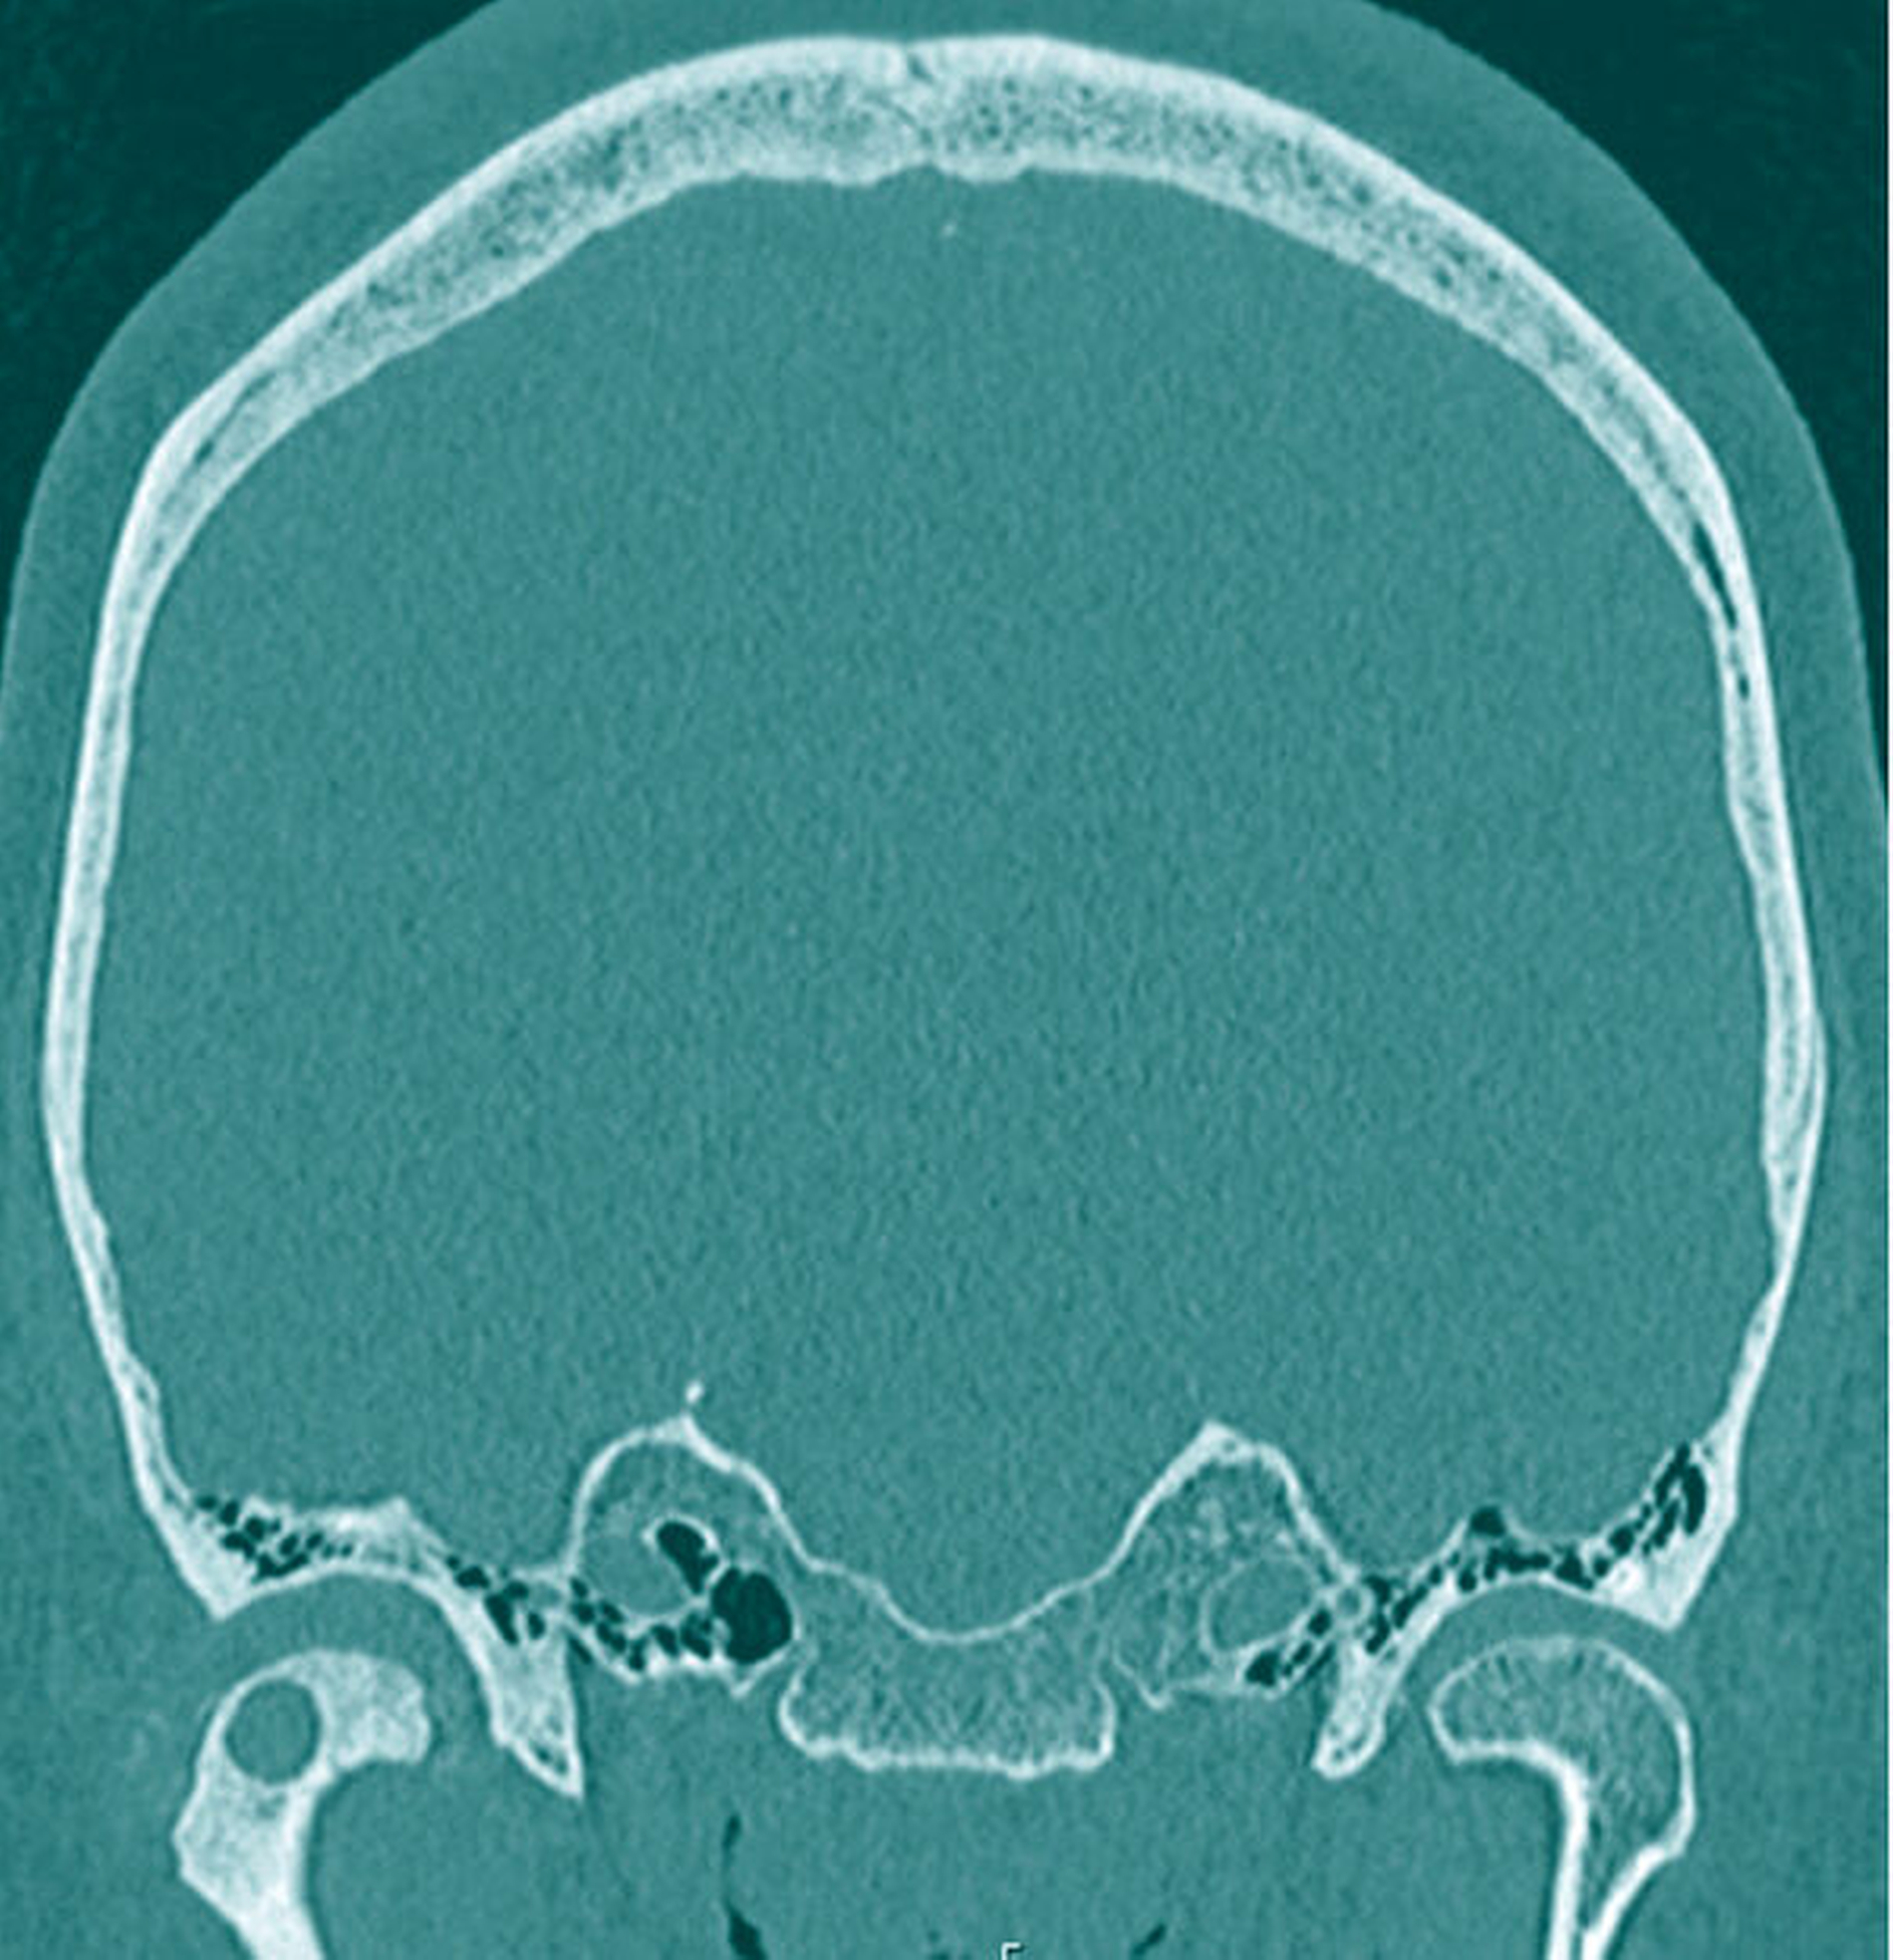

Zur genaueren Eingrenzung und Beurteilung der Knochenstrukturen wurde allerdings eine zusätzliche CT-Untersuchung empfohlen, die im Hinblick auf eine navigationsgestützte Probenentnahme nach kranialem Einbringen von vier Markierungsschrauben durchgeführt wurde. Hierbei wiederum ergab sich in Korrelation mit der bereits durchgeführten MRT-Untersuchung eine Mehrsklerosierung des Capitulums rechts mit geringen Arrosionen im apikalen Anteil und einer glatt begrenzten Zyste. Somit wurde von den radiologischen Kollegen die Verdachtsdiagnose eines Chondrosarkoms aufgestellt (Abbildung 2).